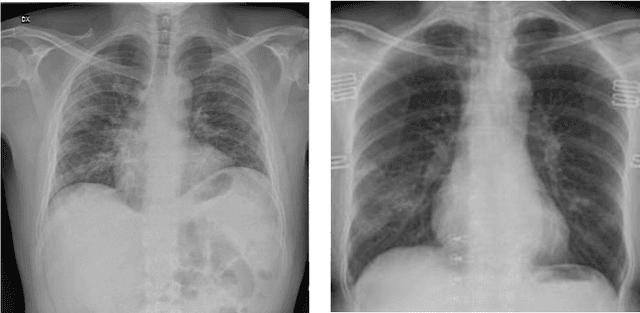

Abstract:The new coronavirus disease (COVID-19) has been declared a pandemic since March 2020 by the World Health Organization. It consists of an emerging viral infection with respiratory tropism that could develop atypical pneumonia. Experts emphasize the importance of early detection of those who have the COVID-19 virus. In this way, patients will be isolated from other people and the spread of the virus can be prevented. For this reason, it has become an area of interest to develop early diagnosis and detection methods to ensure a rapid treatment process and prevent the virus from spreading. Since the standard testing system is time-consuming and not available for everyone, alternative early-screening techniques have become an urgent need. In this study, the approaches used in the detection of COVID-19 based on deep learning (DL) algorithms, which have been popular in recent years, have been comprehensively discussed. The advantages and disadvantages of different approaches used in literature are examined in detail. The Computed Tomography of the chest and X-ray images give a rich representation of the patient's lung that is less time-consuming and allows an efficient viral pneumonia detection using the DL algorithms. The first step is the pre-processing of these images to remove noise. Next, deep features are extracted using multiple types of deep models (pre-trained models, generative models, generic neural networks, etc). Finally, the classification is performed using the obtained features to decide whether the patient is infected by coronavirus or it is another lung disease. In this study, we also give a brief review of the latest applications of cough analysis to early screen the COVID-19, and human mobility estimation to limit its spread.

Abstract:The new coronavirus 2019, also known as COVID19, is a very serious epidemic that has killed thousands or even millions of people since December 2019. It was defined as a pandemic by the world health organization in March 2020. It is stated that this virus is usually transmitted by droplets caused by sneezing or coughing, or by touching infected surfaces. The presence of the virus is detected by real-time reverse transcriptase polymerase chain reaction (rRT-PCR) tests with the help of a swab taken from the nose or throat. In addition, X-ray and CT imaging methods are also used to support this method. Since it is known that the accuracy sensitivity in rRT-PCR test is low, auxiliary diagnostic methods have a very important place. Computer-aided diagnosis and detection systems are developed especially with the help of X-ray and CT images. Studies on the detection of COVID19 in the literature are increasing day by day. In this study, the effect of different batch size (BH=3, 10, 20, 30, 40, and 50) parameter values on their performance in detecting COVID19 and other classes was investigated using data belonging to 4 different (Viral Pneumonia, COVID19, Normal, Bacterial Pneumonia) classes. The study was carried out using a pre-trained ResNet50 convolutional neural network. According to the obtained results, they performed closely on the training and test data. However, it was observed that the steady state in the test data was delayed as the batch size value increased. The highest COVID19 detection was 95.17% for BH = 3, while the overall accuracy value was 97.97% with BH = 20. According to the findings, it can be said that the batch size value does not affect the overall performance significantly, but the increase in the batch size value delays obtaining stable results.

Abstract:Covid-19 is a very serious deadly disease that has been announced as a pandemic by the world health organization (WHO). The whole world is working with all its might to end Covid-19 pandemic, which puts countries in serious health and economic problems, as soon as possible. The most important of these is to correctly identify those who get the Covid-19. Methods and approaches to support the reverse transcription polymerase chain reaction (RT-PCR) test have begun to take place in the literature. In this study, chest X-ray images, which can be accessed easily and quickly, were used because the covid-19 attacked the respiratory systems. Classification performances with support vector machines have been obtained by using the features extracted with residual networks (ResNet-50), one of the convolutional neural network models, from these images. While Covid-19 detection is obtained with support vector machines (SVM)-quadratic with the highest sensitivity value of 96.35% with the 5-fold cross-validation method, the highest overall performance value has been detected with both SVM-quadratic and SVM-cubic above 99%. According to these high results, it is thought that this method, which has been studied, will help radiology specialists and reduce the rate of false detection.